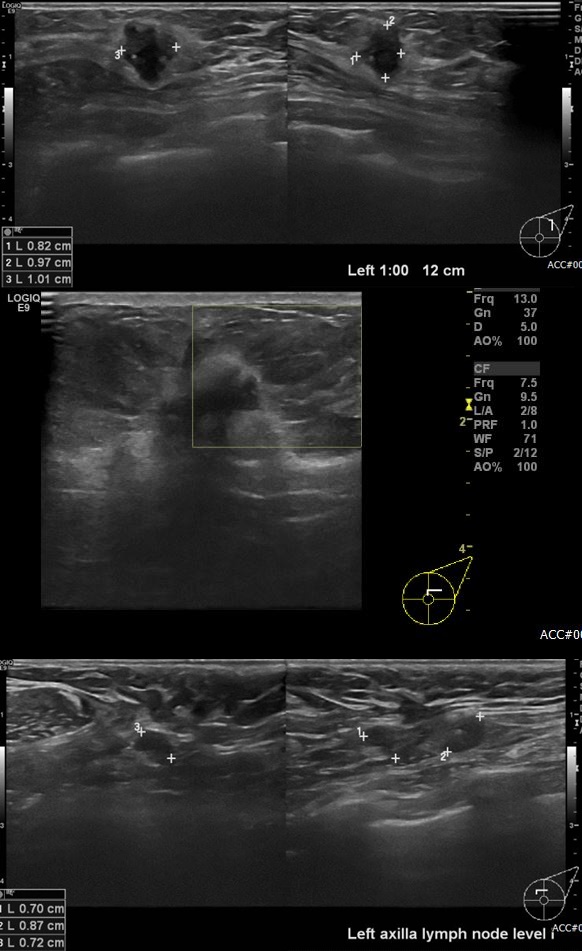

상기환자 건강 검진상 이상 소견으로 내원하신 60대 여성 분으로  좌측 1시 방향에서

12 cm 떨어진 거리의 혹과 1시방향 유두 밑 각각 조직검사 시행하여 좌측 침윤성 유관암

진단 되었으며, 겨드랑이 림프절 비대부 세침검사 시행하여 좌측 전이암 진단 되었습니다.